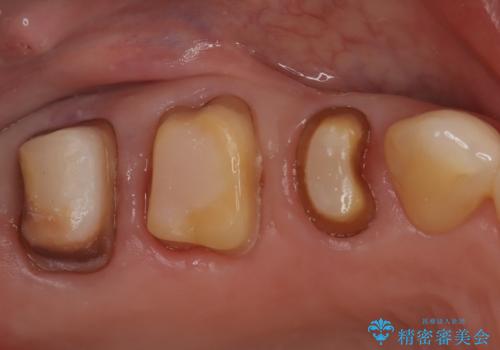

- 古い被せ物をやり変えたいことを主訴に来院されました。

根管治療も行い、きれいな被せ物になり患者さんも喜んでいました。